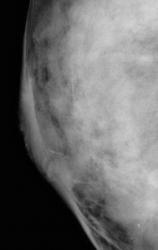

По поводу микрокальцинатов:в конкретном случае это протоковые микрокальцинаты на фоне нарушения архитектоники подкожно-жировой клетчатки( в сравнении с контралатеральной м/железой).В данном случае такое густое скопление микрокальцинатов ( считаю, что не имеет значение их форма в этом случае)+ клиническая картина ( инфильтративное утолщение соска и параареолярной области с иъязвлением ) позволяет заподозрить рак.

Если были бы единичные протоковые кальцинаты, можно направить на УЗИ , если все неплохо, то -динамическое наблюдение.